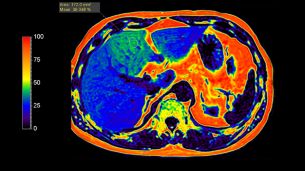

В литературе методика Dixon, реализованная по количеству используемых времен ТЕ, называется 2-точечный Dixon (англ. two-point). Такой подход оказывается крайне восприимчив к неоднородности постоянного магнитного поля B0, так как фазовые сдвиги, вследствие эффектов B0 и химического сдвига, оказываются неразличимы. Существенно снизить влияние неоднородности поля B0 удалось с внедрением методики 3-точечного Dixon (англ. 3-Point Dixon). При этом осуществляется сбор одного in-phase изображения и двух out-phase изображений. Любые фазовые изменения между out-phase изображениями являются следствием неоднородностей поля B0 и используются для корректировки получаемых изображений воды и жира [7]. Этот метод в настоящее время часто используется для быстрого получения изображений с жироподавлением. Методика mDixon может использоваться как с последовательностями градиентного, так и спинового эха и различными взвешенностями изображений. (дополнительно можно ознакомиться на страницах журнала Field Strength (“The next generation fat-free imaging”), (“Одна последовательность, множество преимуществ в МРТ опорно-двигательного аппарата”). Ускорение mDIXON возможно с помощью методов SENCE и Compressed SENCE. Несмотря на большие преимущества методики Dixon, такой подход к количественной обработке оказывается неэффективным для построения карт фракции жира. Основными ограничениями являются отсутствие учета T2* релаксации и состава жирового спектра. Так, при использовании 2- и 3- точечного Dixon учитывается только самый интенсивный сигнал от цепочки метиленовых –СH2- протонов (δ = 1.30 ppm) (рис. 2). В реальности присутствуют сигналы и других функциональных групп жира. Всего в таком спектре присутствует 7 сигналов жира (рис. 2.). Впервые учет вышеперечисленных факторов использовался в работе [8], став доступным с внедрением метода наименьших квадратов в модели, предполагающей несколько компонент жира. Коррекция на затухание Т2* позволяет получить значения фракции жира по протонной плотности (PDFF). Автоматическое построение PDFF карт с использованием 7-компартментной модели жира и коррекции на Т2* доступно с помощью методки mDixon Quant. Пример получаемой карты распределения жира в печени можно найти на рис. 5. В качестве общих рекомендаций к применению данной последовательности необходимо отметить следующие важные параметры: 1) использование малых времен повторения (TR = 5-10 мс) и углов опрокидывания (flip angle FA = 3-5°) для снижения эффектов Т1 релаксации; 2) оптимальное количество времен ТЕ – 6.

Приложение mDIXON Quant обеспечивает быстрое и удобное выполнение неинвазивного количественного анализа жировой ткани печени в режиме 3D, предоставляя трехмерные карты жировой фракции всей печени высокого качества с высоким уровнем точности (±3,5%) и воспроизводимости (±1,4%)¹ даже при коротком T2*, позволяя расширить возможности МРТ. Для облегчения диагностики предоставляются карты релаксации T2*/R2*.